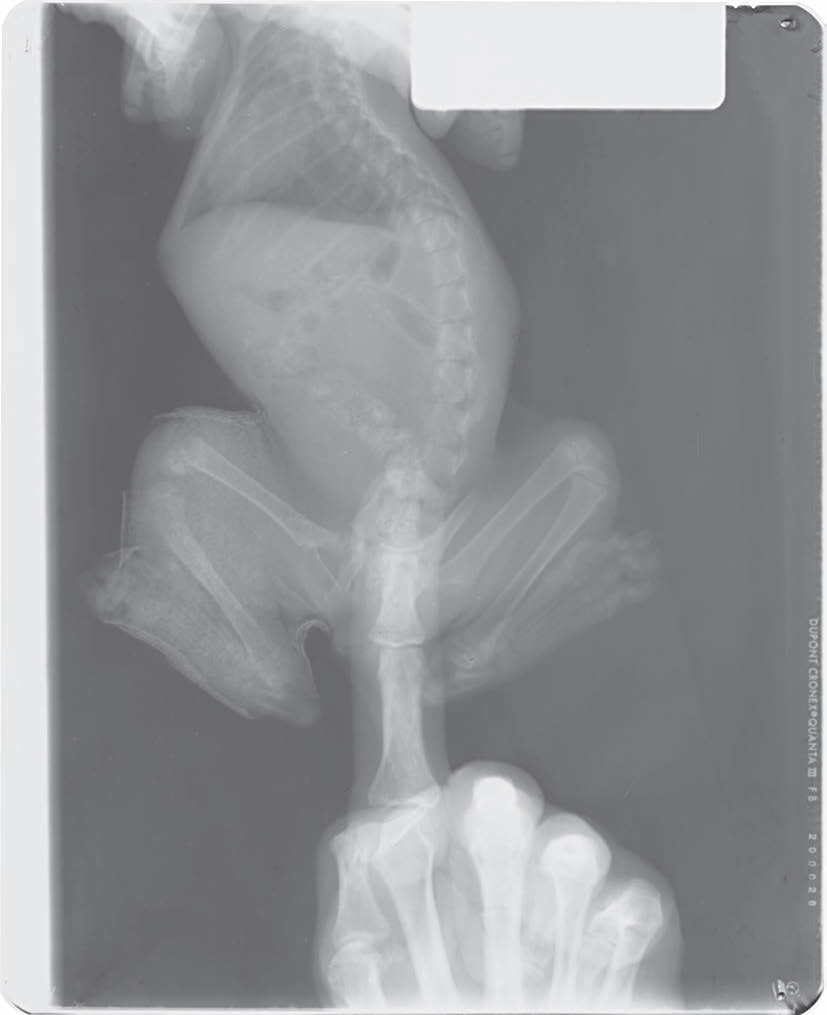

上图4.4——在已镇静动物拍X线片时,适当使用辅助保定。四肢用绳子固定,头和脖子用沙袋固定。在没有任何人员在场的情况下,完成胸部和腹部X线片拍摄。

动物拍片腹部怎么摆小动物X线有哪2种辐射危害?辐射安全有哪3点原则?_https://www.jmylbn.com_新闻资讯_第7张

上图4.5.1——V型槽是胸部、腹部、脊柱和骨盆的腹背位拍片的摆位辅助工具。这个定制的装置由三个有机玻璃板组成,它们以U形组装,然后用泡沫塑料填充。

动物拍片腹部怎么摆小动物X线有哪2种辐射危害?辐射安全有哪3点原则?_https://www.jmylbn.com_新闻资讯_第8张

上图4.5.2——已镇静患犬使用V型槽拍摄腹背位的胸片。这种伸展的姿势比放在又硬又宽的桌子上要容易。注意使用绳索将腿部固定到位,并放置沙袋以稳定头部。这只犬的X线片也是无人在场的情况下完成拍摄。